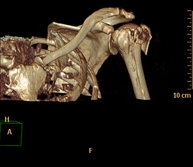

- Shoulder CT

Radiological examination based on an X-ray system and detectors that rotate around the patient, reconstructing the images by computer (multidetector computed tomography - MDCT) to study the bones, muscles and joints of the shoulder.